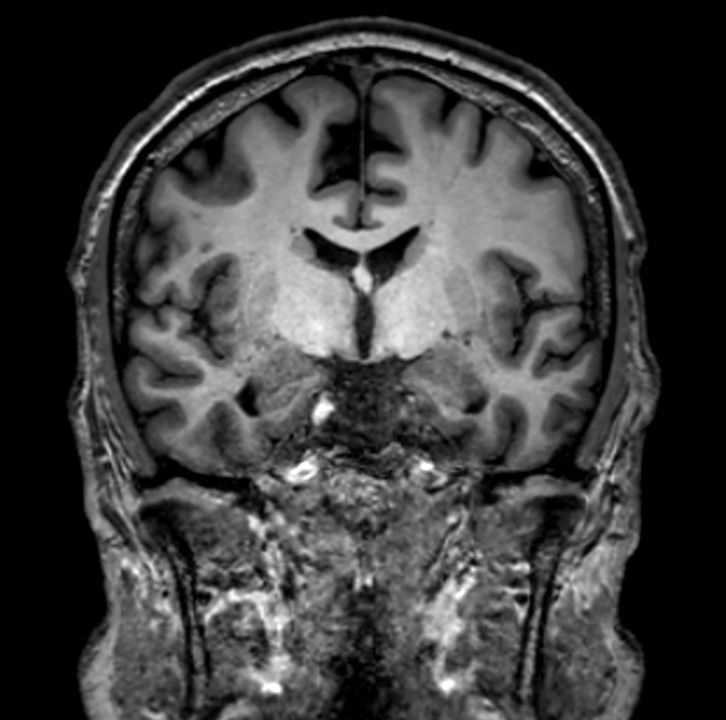

3D VIEW - T1w TSE (coronal reformat)